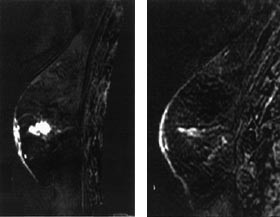

Brystkreftsvulster som er større enn 5 cm eller som vokser inn i hud eller brystvegg, behandles vanligvis med kjemoterapi eller anti-hormonbehandling før kirurgi. På grunn av problemer med å differensiere ødem og arrvev fra vitalt tumorvev er responsen på denne behandlingen vanskelig å vurdere, både klinisk og med konvensjonelle bildemetoder. Flere studier tyder på at kontrastopptak ved MR samsvarer godt med vitalt tumorvev (32, 33). Ved å registrere endringer både i kontrastopptaksmønster og tumorstørrelse er trolig MR den beste bildediagnostiske metoden for å evaluere behandlingseffekten (fig 4).